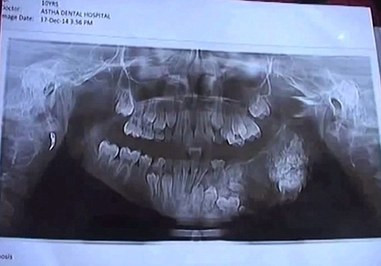

تصاویر/ پسری با ۸۰ دندان اضافی!

یک پسر ۷ ساله هندی در شهر بمبئی این کشور پس از تحمل درد فراوان در فک و دهان خود با مراجعه به پزشک متوجه شده است که دارای ۸۰ دندان مخفی و ظاهر در دهان خود است. این کودک دارای ۸۰ دندان تنها در فک بالای خود است و پزشکان در یک جراحی ۴ ساعته دندان‌های زائد را از دهان او خارج کردند. چندی پیش در ماه ژوئیه سال ۲۰۱۴ یک پسر ۱۷ ساله هندی دیگر با ۲۳۲ دندان مورد عمل جراحی مشابهی قرار گرفته بود.